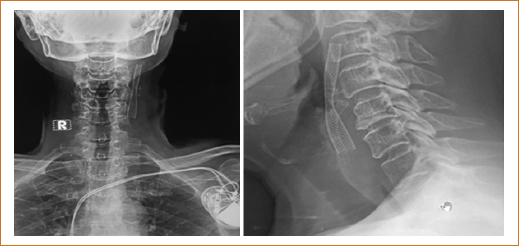

El 25 de enero de 2020 se procedió a practicar panangiografía de troncos supraaórticos y carótidas, bajo el siguiente protocolo intervencionista: cateterismo de vasos del cuello con panangiografía por vía femoral derecha, usando proyecciones ortogonales en anteroposterior, lateral, oblicuas y posiciones especiales usando un catéter guía MATCH 1 de calibre 7 Fr con ayuda de una guía Terumo de 0.032”. En la arteria carótida común derecha no se observaron placas ateromatosas, y tampoco en su ramas interna y externa, la arteria carótida interna común izquierda sin lesiones, la arteria carótida externa izquierda sin lesiones, la arteria carótida interna izquierda con lesión estenótica grave del 90% en su origen y placa focal extensa sin afectación de la bifurcación (Fig. 1). Las arterias subclavias no presentaban zonas de estenosis significativas. Se llevó a cabo un cateterismo cardiaco protocolario por vía radial derecha realizando stenting carotídeo izquierdo con ascenso de un catéter guía multipropósito Match 1 de calibre 7 Fr con una guía hidrófila Terumo de 0.032” posicionándose en la arteria carótida común izquierda 3 cm por debajo de la bifurcación. Se practicó ascenso wallstent 7 × 40 mm con una guía ChoICE PT extrasoporte de 0.014” y se liberó un stent de distal (arteria carótida interna izquierda) a proximal (arteria carótida común izquierda), observando una estenosis residual del 50%, por lo que se avanzó un balón HIRYU de 5 × 10 mm con el que se posdilató a 16 atm, con un resultado final exitoso de solo un 20% de estenosis residual (mejoría del 70%) (Fig. 2). Termina el procedimiento asintomática cardiovascular e íntegra neurológicamente, se retira el introductor femoral y se coloca un dispositivo de cierre vascular Angio-Seal de 6 Fr. Hallazgos: 1) tronco coronario izquierdo ligeramente sinuoso, sin lesiones significativas; 2) arteria circunfleja ligeramente tortuosa, sin zonas de estenosis; 3) arteria descendente anterior un poco más sinuosa, sin zonas de estenosis; y 4) arteria coronaria derecha de trayecto muy regular, de muy buen calibre, sin imágenes de estenosis. Se concluyó el cateterismo cardiaco sin incidentes clínicos ni complicaciones, con el sumo cuidado de optimizar la dosis del medio de contraste (solo se usaron 25 ml).

Figura 1. Arteria carótida interna izquierda.